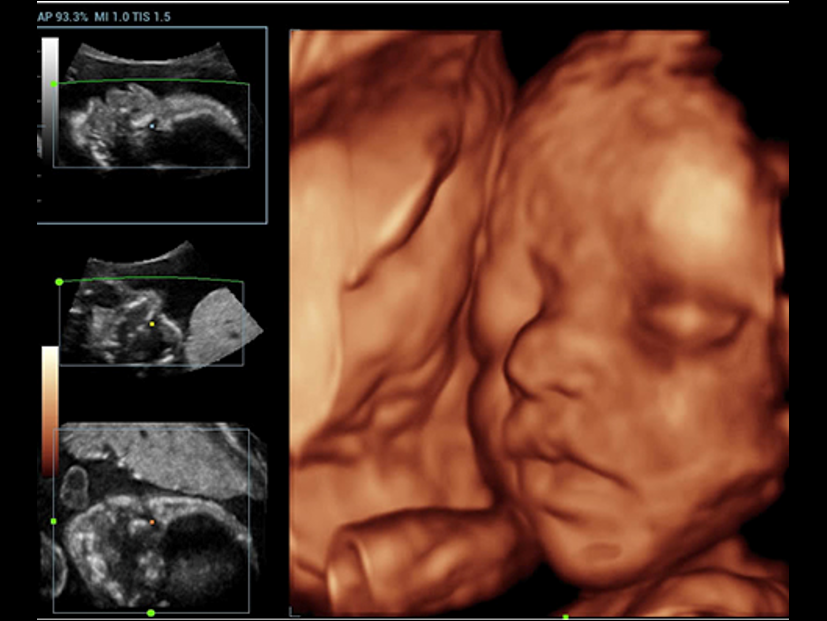

Fin dalla sua fondazione Mindray esplora continuamente nuovi modi per migliorare l'affidabilit├Ā diagnostica. Equipaggiata con la pi├╣ rivoluzionaria tecnologia ZONE Sonography?, la nuova piattaforma ZST+ di Resona 7 porta la qualit├Ā dell'immagine ecografica ad un livello superiore con l'acquisizione per zone e l'elaborazione dei dati canale.

Oltre alla qualit├Ā delle immagini di livello eccellente, Resona 7 migliora anche le capacit├Ā di ricerca clinica il rivoluzionario V Flow per la valutazione emodinamica vascolare, e l'acquisizione piani pi├╣ intelligente dal set di dati 3D per la diagnosi del sistema nervoso centrale fetale. Combinando il pi├╣ intuitivo funzionamento multi-touch basato su gesti e tutte le caratteristiche cliniche essenziali, Resona 7 sta veramente portando nuove tendenze nellŌĆÖinnovazione dellŌĆÖecografia.